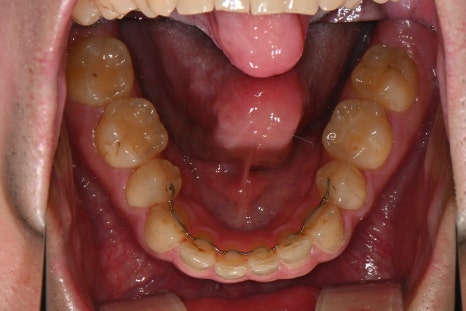

오른쪽 사진: 왼쪽 아래쪽 철사가 끊어지고, 오른쪽은 유지장치가 완전히 떨어져 치아 사이에 틈이 생긴 모습입니다.

시간이 지나며 유지장치가 약해져 제 기능을 못하고 있었어요.